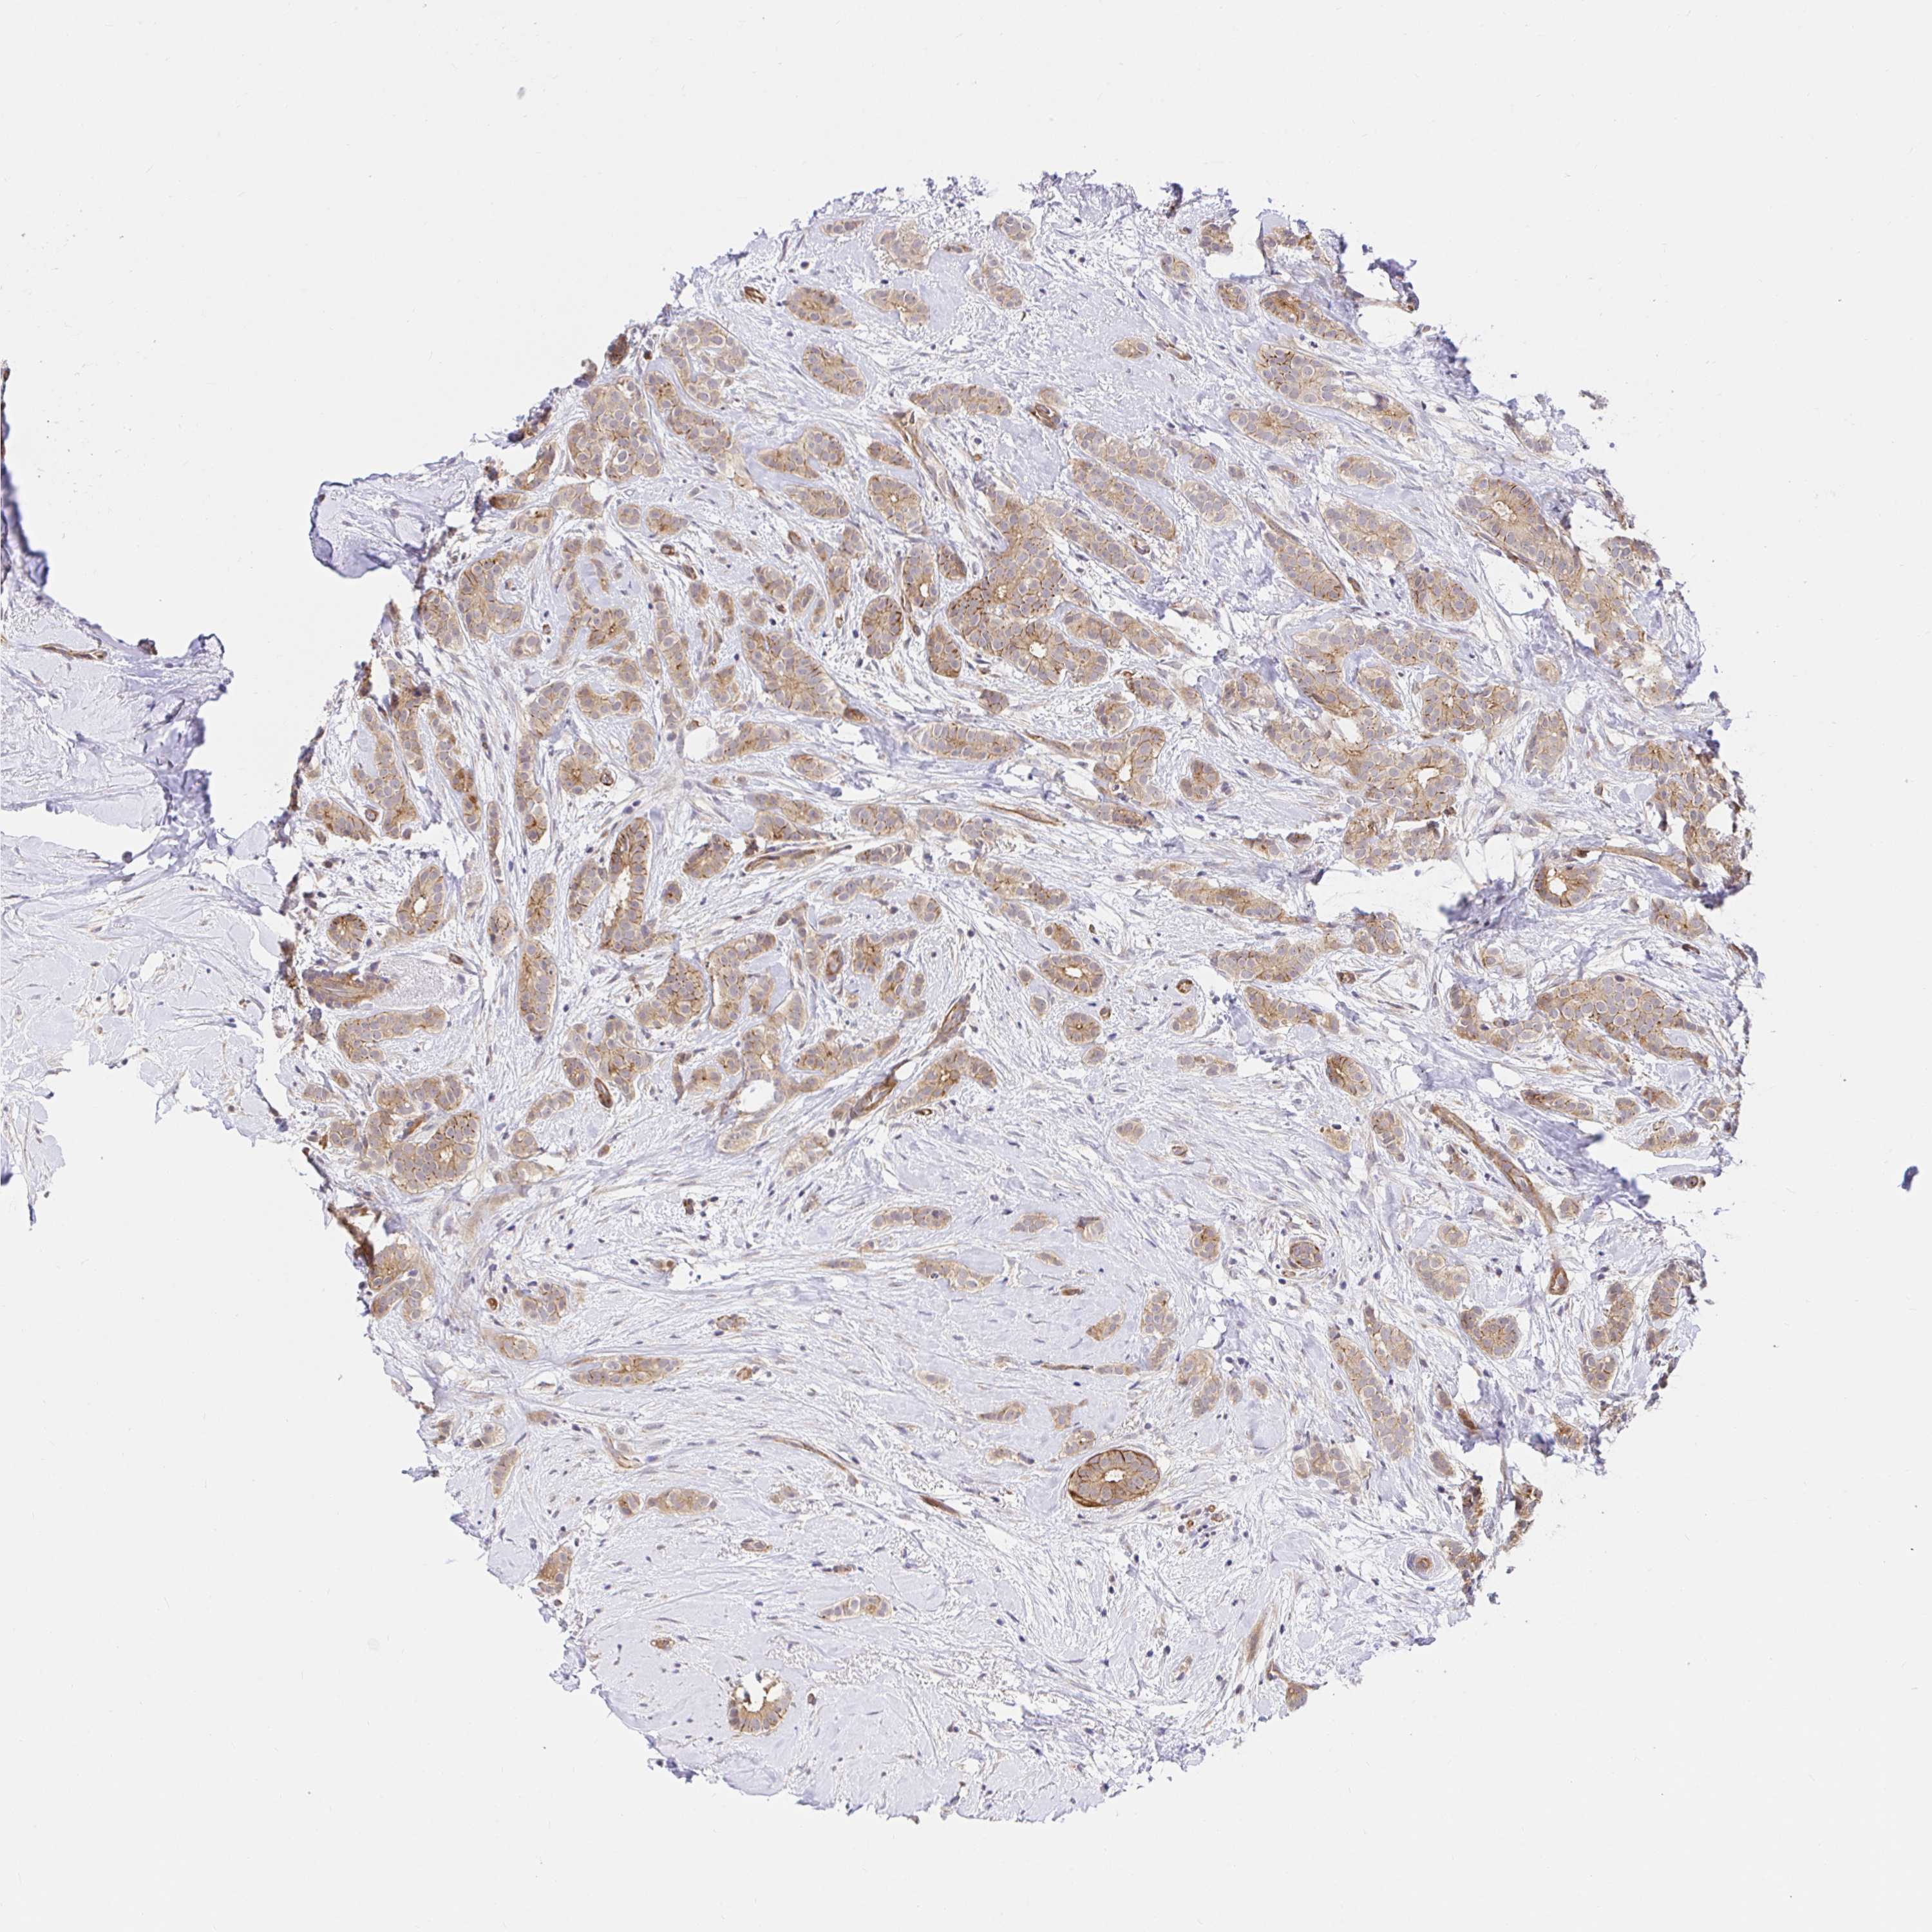

CANCER BREAST CANCER Show tissue menu

BRCA TCGA BRCA VALIDATION PROTEIN EXPRESSION

Breast cancer

Human cancer

TRIM55 is not prognostic in Breast Invasive Carcinoma (TCGA)